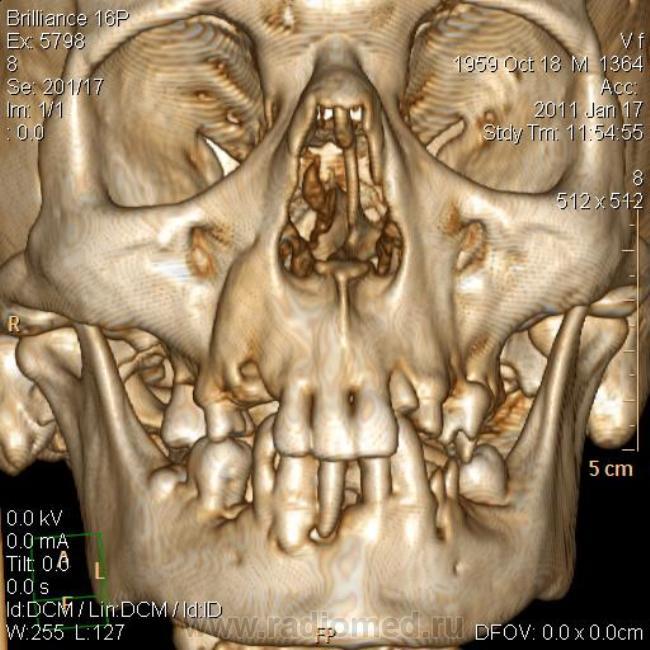

КТ головного мозга. Случайная находка. Жалоб "на челюсти" нет.

Мужчине 51 год. Периферический рак легкого. Очаговых изменений головного мозга не нашла. Пациент не критичен к своему состоянию (никуда не поеду, пусть как есть остается), поэтому отсутствие жалоб еще ничего не значит.

Контуры внутренние деструктивной полости изъеденные, кость вздута, но внешне не видно. В центре уровень?  с плотностью 30 ед.Н. Адамантинома? С зубными делами практически не сталкиваюсь. Нужна Ваша помощь. Какие будут идеи, уважаемые коллеги?

На мой взгляд процесс был, да прошел. Состояние после апикальной кисты удаленного зуба

Я думаю, это радикулярная киста с вторичным гиперостозом стенок воспалительного характера. Не уверен, что это состояние можно назвать остеомиелитом.

На метастаз и адамантиному непохоже.

До кабинета стоматолога дело не дошло. Просто триллер получился... пациент отказался от осмотра, мол, выписывают, как заболит - пойду в поликлинику. А когда пришел за диском с DICOM, у меня в ординаторской была стоматолог. Ей-богу случайно!)) Осмотрели ротовую полость. Хоромlaugh. Слизистая совершенно нормальная. Потом мы тем же хором его анамнестически "пытали" - каждое слово вытягивая словно клещами. Затащить в стомат.кресло не удалось, но вывод стоматолога после просмотра КТ таков - вероятнее всего, киста с периодическим нагноением.

Случай в свое время прошел мимо. Интересный случай. Да, и в нижней челюсти, по всей видимости, имеет место патология.